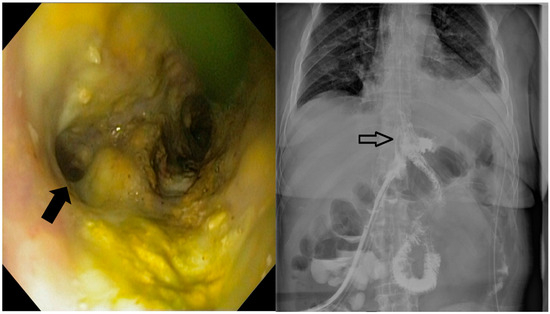

These procedures were performed by interventional endoscopists using an endoscope equipped with a CO2 inflator. During the diagnostic phase, the fistula (Figure 2) was confirmed and characterized through endoscopic visualization and contrast opacification under fluoroscopy. Key aspects assessed included the size of the orifice (<1 cm, 1–2 cm, >2 cm), the condition of the edges (whether necrotic, inflammatory or fibrous), the presence of pus and any drainage. Based on these findings, the therapeutic phase involved placing a covered metallic stent, applying a clip or using a combination of treatments. The specific endoscopic devices used, and the absence of residual leakage after contrast injection at the end of the procedure, were documented.

Figure 2. The endoscopic appearance of an eso-jejunal anastomotic fistula following surgical resection of a gastric neoplasm, along with the radiological findings after oral contrast administration.